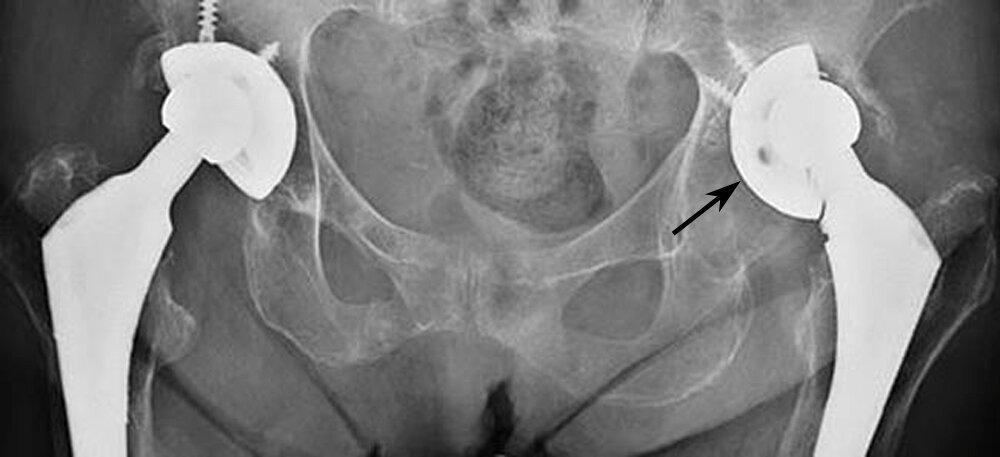

- X-rays: Used to identify loosening, fractures, malalignment, or component wear.

- MRI or CT scan: Provides detailed images of soft tissue, bones, and the position of the implant components.